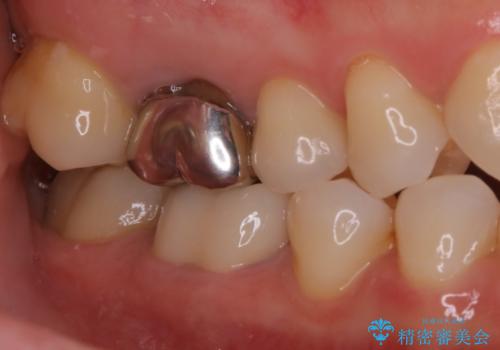

- 歯が欠けてしまったと来院された方です。

メタルインレーが一部欠けており、その下には大きな虫歯ができていました。

再精密根管治療もご提案しましたがご希望されなかったため、今回は土台と被せ物のみ治療介入しました。

根管治療をした歯は神経のある歯と比較して強度が下がり、長期的に破折のリスクが高まると言われています。破折のリスクを軽減させるため、根管治療を行った歯に対しては歯冠をすべて覆うクラウンという被せ物にて補綴処置を行います。